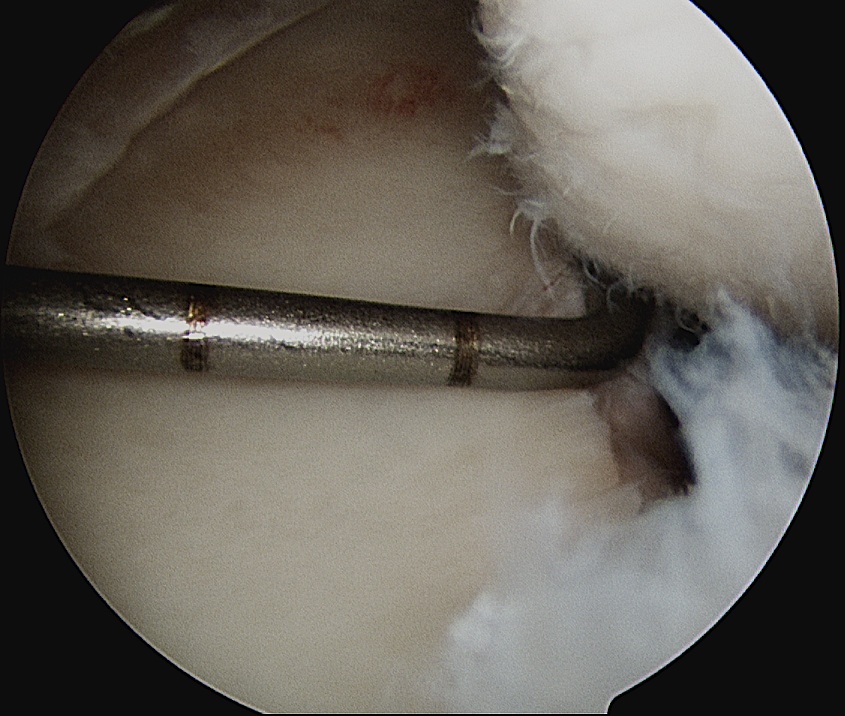

Pass sutures and tie knots

Typically curved suture passers

Aim to tighten capsule medially and superiorly onto glenoid